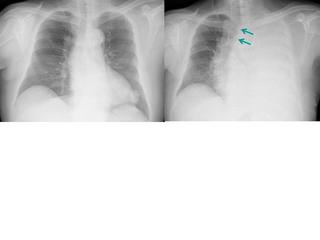

わかりにくいかもしれませんが、このあたり。

気管が追いにくい、無くなっているようにも見えます。

気管狭窄ですね。こういう所見もレントゲンで捉えることができるのです。